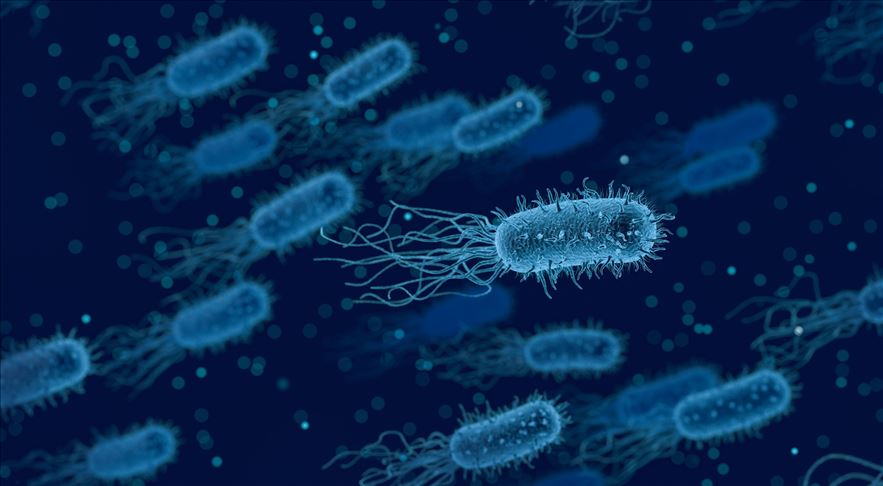

Lejyoner hastalığı nedenleri nelerdir?

Etken bakteri olan Legionella genellikle göller, nehirler ve akarsular dahil tatlı su ortamlarında bulunur. Legionella ayrıca toprakta da yaşayabilir, fakat çoğu insan topraktan bakteri kapmaz. Lejyoner hastalığını ev tesisat sistemleri yoluyla kapmak mümkün olsa da, çoğu salgın otel gibi toplu yaşama dahil büyük binalarda meydana gelir. Çünkü karmaşık dağıtım sistemleri bakterilerin daha kolay çoğalıp yayılmasına izin verir.

Ilık suda kolaylıkla çoğalabilen bakteri, genellikle bir binanın kirlenmiş su dağıtım sistemi yoluyla yayılır. Fakat hastalık havada asılı duran su damlacıklarının solunması yoluyla insanlara bulaşır. Bakteri o kadar küçüktür ki, su buharı gibi küçük su damlacıklarının içine yerleşerek havaya karışabilir. Kontamine suların bulunduğu sauna, hamam veya kaplıca havuzu gibi sıcak sulardan çıkan buhar damlacıklarının solunması ile bakteri akciğerlere ulaşır. Nadiren bakteri ile kontamine suların içilmesi sırasında soluk borusuna kaçmasıyla da bulaşabilir. Kişiden kişiye yayılım söz konusu değildir. Uygun şekilde bakımı yapılmadığında lejyonella için temel üreme alanları şunları içerir:

- Spa ve termal havuzlar

- Havalandırma sistemleri

- Manav reyonlarında bulunan sis püskürtme sistemleri

- Dekoratif fıskiyeler

- Otel, hastane ve bakım evlerinin su dağıtım sistemleri